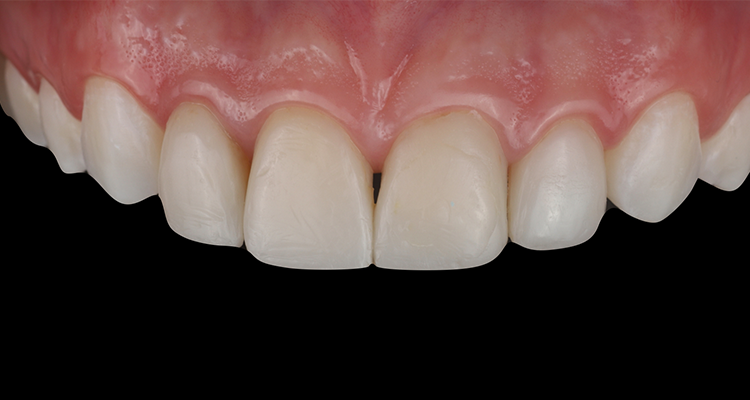

11 | Aspecto final das restaurações após acabamento e polimento.